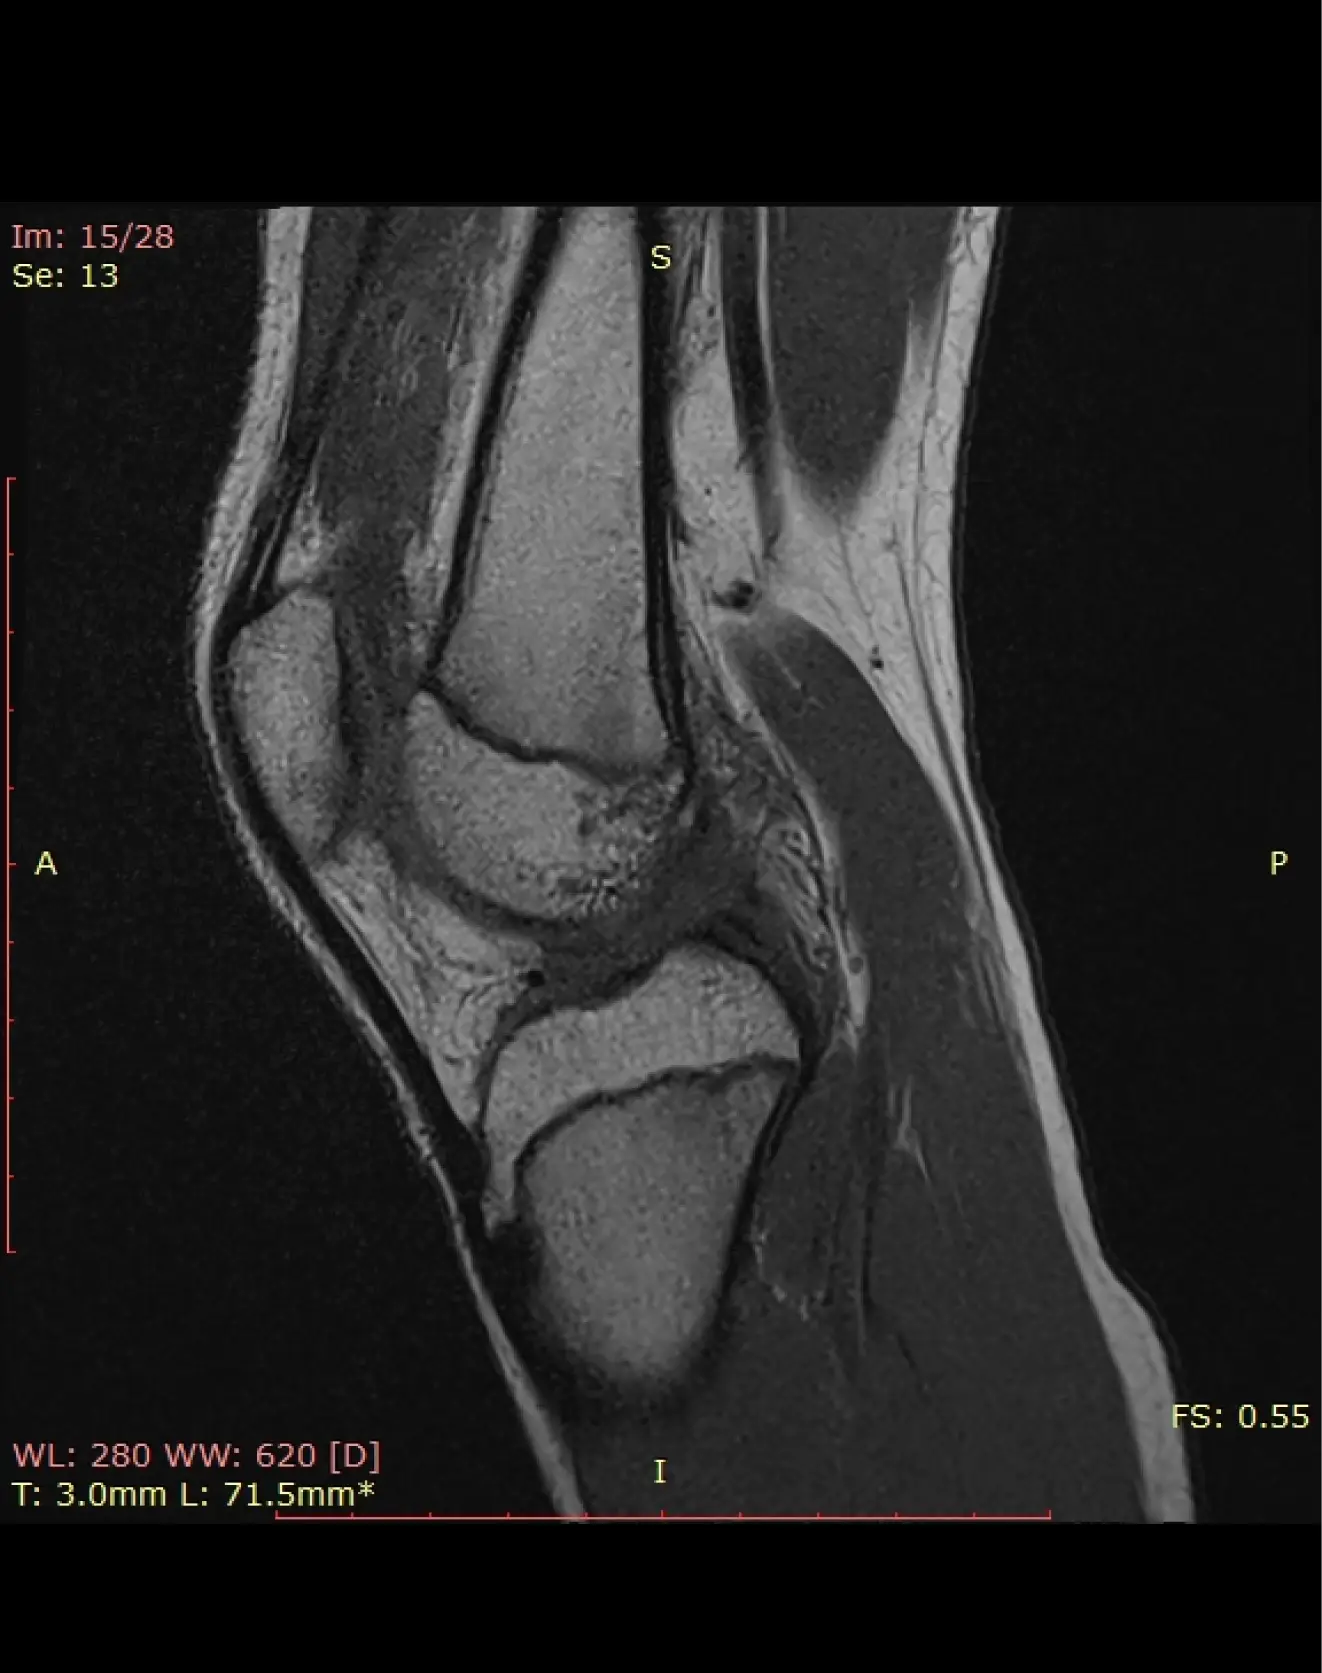

МРТ коленного сустава

Визуализация костей коленного сустава включая надколенник, суставной капсулы, менисков, связок и сухожилий, параартикулярных тканей.